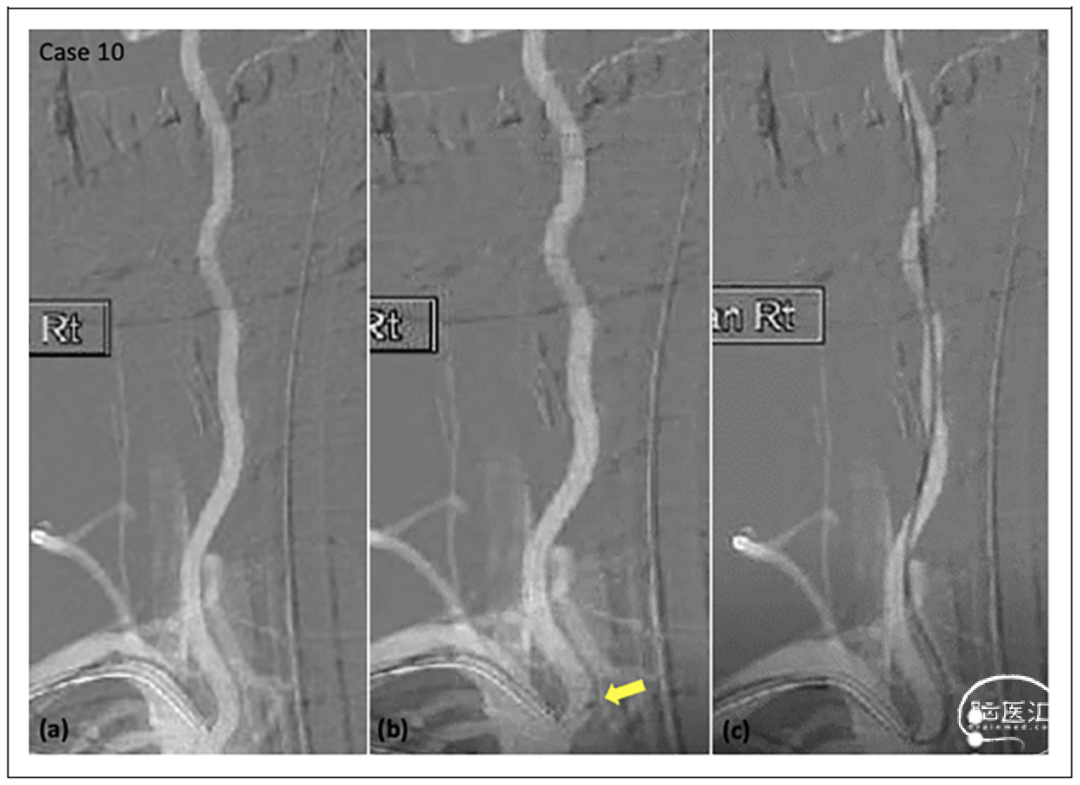

在其他专业中确实存在可操控导管,尤其是在心脏电生理学中,此类导管对于心脏电路图绘制和消融至关重要。早在2000年代初就推出了一种名为Enzo的可操控导管,用于神经血管,但后来被停产了。随着微型化的持续推进和海波管以及肌腱技术的发展,可操控和扭控微导管现在已经进入市场。这篇回顾性研究报告了单个高容量综合性卒中中心的前10例临床病例,概述了新型Bendit 21微导管(Bendit Technologies, Ltd, Petach Tikva, Israel)的观察结果,该导管于2019年获得了美国食品和药品管理局(FDA)的批准。

结果

病例集锦